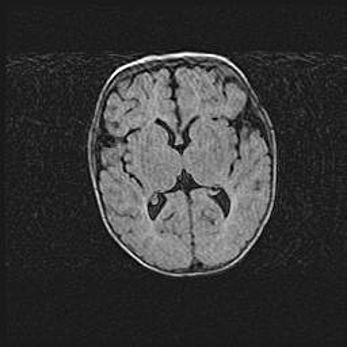

Множественные кисты обоих полушарий головного мозга, наибольшая из них в правой затылочной области. Ассиметричная атрофическая гидроцефалия.

Возраст: 7 месяцев

Вес: 5660 г

Пол: мужской

Окружность головы: 41,5 см

Срок гестации: 28-29 недель

Кисты головного мозга развиваются в результате многоочаговых некрозов вещества мозга и возникают вследствие перенесенной перинатальной инфекции, менингитов, энцефалитов, асфиксии, родовой травмы, расстройств мозгового кровообращения различного генеза. Образованию кист в веществе головного мозга плодов и новорожденных способствуют такие факторы, как высокое содержание в нем воды, недостаточная (или отсутствие) миелинизация и слабая астроглиальная реакция на повреждение.

Кисты могут сочетаться с гидроцефалией и другими поражениями головного мозга.